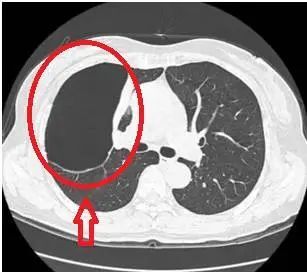

最近常常有患者拿著胸部CT來(lái)咨詢關(guān)于肺大泡的一些問(wèn)題,很多人在網(wǎng)上查閱資料后發(fā)現(xiàn)肺大泡無(wú)法用藥根治,頓時(shí)茶飯不思,在這里我們帶大家正確認(rèn)識(shí)肺大泡。什么是肺大泡?肺大泡,是指由于各種原因?qū)е路闻萸粌?nèi)壓力升高,肺泡壁破裂,互相融合,在肺組織形成的含氣囊腔。肺大泡定義為擴(kuò)張狀態(tài)下,直徑超過(guò)1cm的肺內(nèi)氣腔(圖1),巨型肺大泡是指至少占據(jù)一側(cè)胸腔30%的大泡(圖2)肺大泡的常見(jiàn)原因是什么?1.氣管的炎性病變?nèi)绶窝住⒎谓Y(jié)核、慢性支氣管炎等,因炎性病變,氣管出現(xiàn)水腫、狹窄,造成管腔部分阻塞,產(chǎn)生活塞作用,空氣能進(jìn)入肺泡而不易排出去,使之肺內(nèi)壓增高。2.吸煙、空氣污染對(duì)于長(zhǎng)期吸煙及其他有害氣體和職業(yè)粉塵吸入史的患者,人體在吸入這些有害的氣體、細(xì)顆粒物后,這些物質(zhì)經(jīng)過(guò)氣管、細(xì)支氣管,最終在肺泡停留沉積下來(lái),它們會(huì)長(zhǎng)時(shí)間的刺激、破壞正常的肺泡結(jié)構(gòu),肺泡壁破裂,從而形成肺氣腫,隨著破壞的進(jìn)一步持續(xù),這些肺氣腫也將進(jìn)一步破壞,融合成片,從而最終形成肺大泡。3.原發(fā)性肺大泡原發(fā)性肺大泡,可能與肺發(fā)育不良有關(guān),多見(jiàn)于體形瘦高的青少年,其原因可能與青春期發(fā)育過(guò)程中,骨骼生長(zhǎng)過(guò)快,肺相對(duì)生長(zhǎng)緩慢,在胸頂和肺尖部有一個(gè)筋膜過(guò)渡牽拉肺尖部組織,導(dǎo)致該處肺組織的肺泡發(fā)育不良形成肺大泡。肺大皰如何治療呢?肺大泡一種不可逆轉(zhuǎn)的肺部病損,一般不能自愈,且目前尚無(wú)特效藥物治療,手術(shù)是治療肺大泡唯一有效的方法,但不是所有的肺大皰均需手術(shù)質(zhì)量。如一些較小的、局限的、數(shù)量少的肺大泡,多不會(huì)引起臨床癥狀,通常不需要治療。由氣道炎癥、肺氣腫等病變導(dǎo)致的肺大泡,需要積極治療原發(fā)病。肺大泡如果大于胸腔的1/3,就被稱為巨大的肺大泡,可能對(duì)周圍的組織形成較大的壓迫,甚至對(duì)生命產(chǎn)生威脅,這種情況要盡快進(jìn)行手術(shù)治療。肺大皰患者的注意事項(xiàng)1.吸煙及空氣污染是肺氣腫的首要誘因,因此遠(yuǎn)離煙草及空氣污染能夠減緩進(jìn)程;2.平時(shí)不要做劇烈的運(yùn)動(dòng),不要手提重物,不要突發(fā)性的大聲咳嗽及大笑,避免肺大泡破裂,產(chǎn)生自發(fā)性氣胸;3.適當(dāng)鍛煉身體,增強(qiáng)身體的抵抗力和免疫力,根據(jù)自身情況,參加一些適當(dāng)?shù)捏w育活動(dòng),注意營(yíng)養(yǎng),多進(jìn)食優(yōu)質(zhì)蛋白質(zhì)以及含維生素較高的食物,提高機(jī)體抵抗力;4.避免呼吸道感染,每次呼吸道感染后肺功能都受影響。對(duì)于慢性阻塞性肺疾病、支氣管哮喘等原發(fā)性疾病,積極治療原發(fā)病,改善肺功能;5.若出現(xiàn)由肺大泡破裂導(dǎo)致的胸痛、胸悶、呼吸困難等不適癥狀,應(yīng)及時(shí)到醫(yī)院治療。?